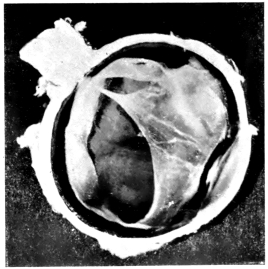

PLATE III.

16.

ABUNDANT EXUDATE INTO VITREOUS CAVITY

curly bracket span

42

17.

LENS FIRMLY FIXED BY ORGANIZED EXUDATE

18.

LENS FIRMLY FIXED BY ORGANIZED EXUDATE, BUT IN UNUSUAL POSITION

19.

TOTAL DETACHMENT OF RETINA, WITH CYST FORMATION

20.

RECLINED LENS LYING IN FRONT OF THE HYALOID BODY

21.

RECLINED LENS LYING IN FRONT OF THE HYALOID BODYxii